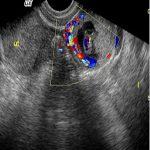

输卵管妊娠(宫外孕输卵管妊娠)是最常见的异位妊娠,即受精卵种植于输卵管。以壶腹部妊娠为最多,占50%-70%;其次为峡部,占30%-40%;伞部、间质部最少见,占1%-2%。今天跟大家分享一例间质部妊娠的图片: